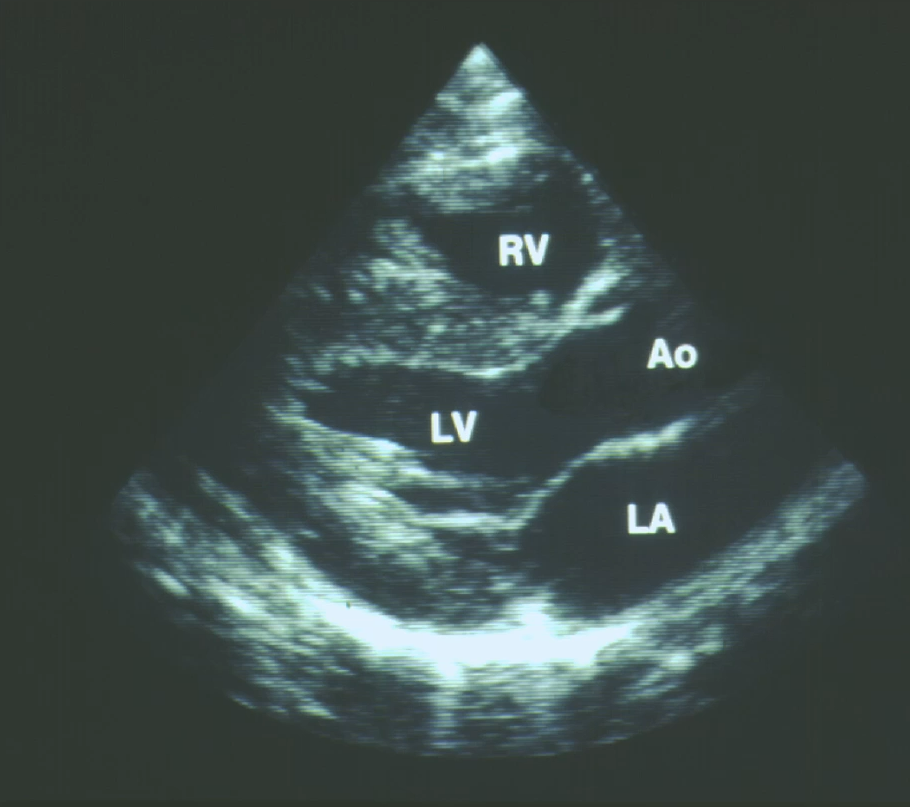

• Echocardiogram pt2:

• this echocardiogram shows the mitral valve closed, preventing blood to flow from the left atrium to the left ventricle, representing systole